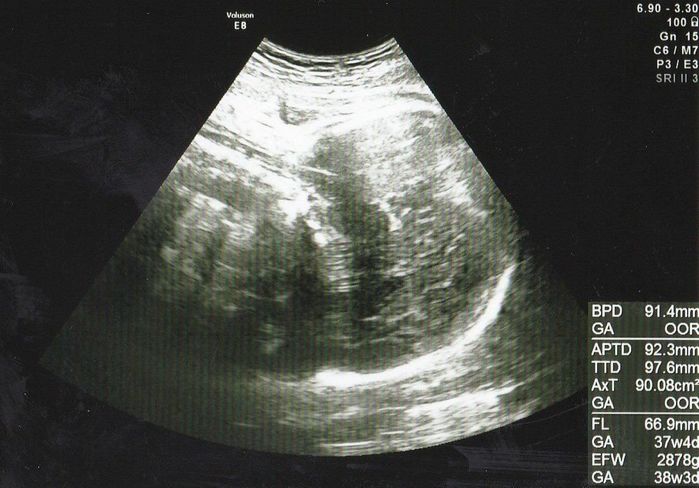

妊娠36週目エコー写真 「もう生まれても大丈夫」と、先生からお墨付き

推定体重=2878g

右側に頭、体は背中を向けて左側に、手を顔の前においているエコー画像です。赤ちゃんの体重はもうすぐ3kgというところ。先生から「(大きさとしては)もう生まれても大丈夫」と言われましたが、陣痛などの兆候は全くなく、出産がいつか、いつかとそわそわしていました。